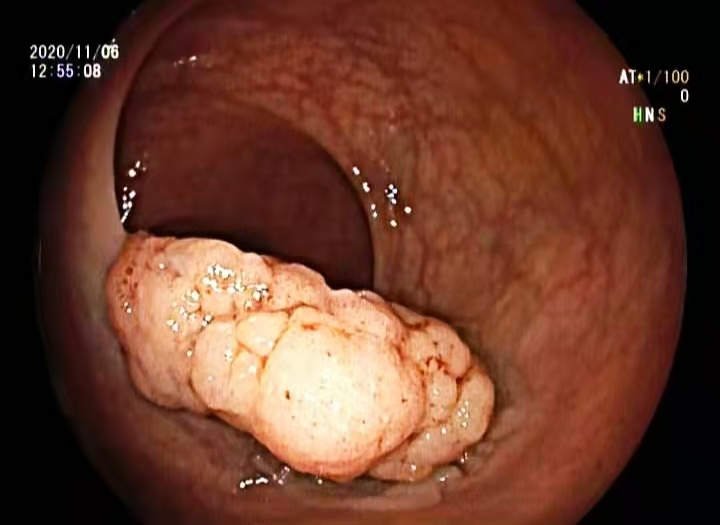

11月06日,内镜下黏膜剥离术由消化内科学科带头人陈星博士主镜操作。观察患者病情后,陈星博士成竹在胸,只见他标记、黏膜下注射、剥离,一系列高难度动作一气呵成,整个手术仅用时30分钟,患者无任何不适。

术后病理回报:高级别内瘤变,未见黏膜下浸润,病理诊断直肠黏膜内癌。

术后结肠镜显示